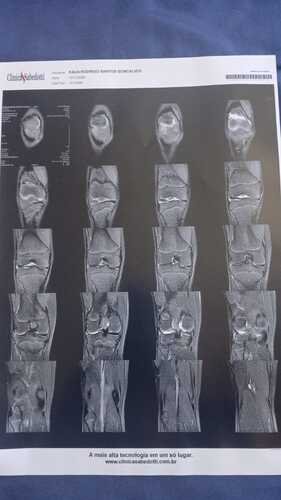

Eu sou Emanuelly, criei essa vakinha para conseguir juntar o valor total ou parcial de um procedimento cirúrgico chamado Artroscopia no joelho direito do meu irmão mais novo, ele sofreu um acidente no colégio Monteiro Lobato onde é aluno e estuda, infelizmente atualmente ele não consegue andar, a perna dele está perdendo massa muscular e perdeu os movimentos, ele está fazendo fisioterapia mas precisa urgentemente da cirurgia pra não ficar com sequelas, e não acabar atrofiando a perna direita dele.